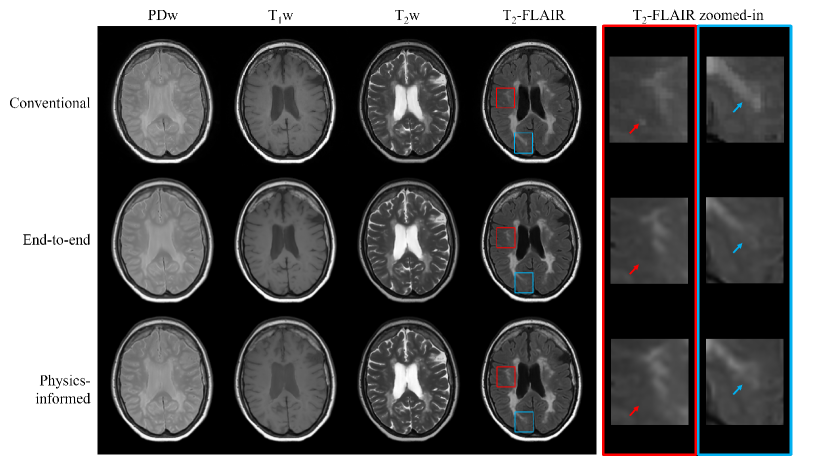

The end-to-end and physics-informed approaches do not display large visual differences, for example, as demonstrated for a multiple sclerosis patient in Fig. 5. The conventional and synthetic PDw and T1w images lack contrast between the lesions and the surrounding healthy tissue. The CSF of the physics-informed T1w contrast was consistently hyperintense compared to the conventional contrast. Both synthetic T2w contrasts accurately capture almost all lesions present in the conventional contrast, but for the T2-FLAIR contrasts, some smaller lesions were missed (Fig. 5, red arrows) and hypointense or blurred (Fig. 5, blue arrows).

Here, a more detailed analysis of the T2-FLAIR contrasts is provided, where the artifact counts are determined using manual inspection of the images. Motion artifacts were detected for 17 out of 43 test subjects (40%) in the conventional contrasts, which were not observed for the synthMRI of any subject (Fig. 6a). CSF flow artifacts are present for 43 subjects (100%) in the synthMRI (Fig. 6b). Grid-like (chessboard) artifacts were introduced in the brainstem for 23 (53%) and 4 (9%) subjects for the physics-informed and end-to-end approach, respectively (Fig. 6c). Similar chessboard patterns were observed in the parenchyma of 4 (9%) subjects for the physics-informed method. Finally, synthMRI (especially the end-to-end approach) can appear blurrier than the conventional contrasts, for example, the basal ganglia structures (Fig. 6d). This finding has been quantitatively confirmed in a study reported in the supplementary materials investigating image sharpness. Regarding pathologies, both synthMRI methods sometimes miss or result in hypointense lesions with a smaller volume, for example, in epilepsy or multiple sclerosis patients (Fig. 6e-f). Also, more prominent, complicated pathologies such as a stroke can result in inaccuracies. Although the gross shape is captured, hypointensities and blurriness were observed (Fig. 6g). Finally, both synthMRI methods were found to result in an unrealistic suppression of tumor contrast for 4 out of 10 patients (40%) (Fig. 6h).